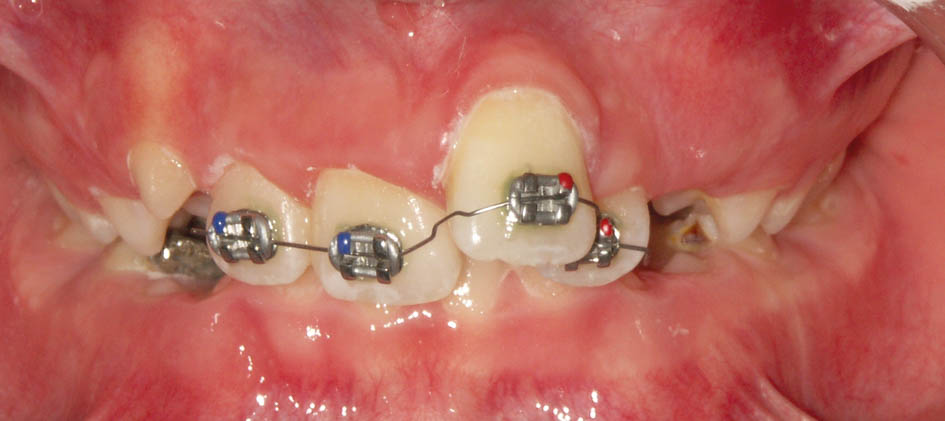

در این مواقع باید دندانهای قدامی را پروترود کنید. میتوانید یک پلاک آکریلی بسازید و Z Spring پشت قدامیها میگذارید یا چند تا براکت با یک سیم 0.012 سوپرالاستیک بگذارید. طبیعی است که گذاشتن چند براکت (شکل 74-5 و 75-5) خیلی سریع و در کمتر از 2 ماه جواب میدهد و نیاز به همکاری از جانب بیمار خیلی کمتر است.

شکل 74-5: چسباندن چند براکت و قراردادن سیم 0.012 سوپر الاستیک برای ساختن اورجت (تبدیل بیمار کلاس II/2 به II/1).

شکل 75-5: نمای روبروی بیمار